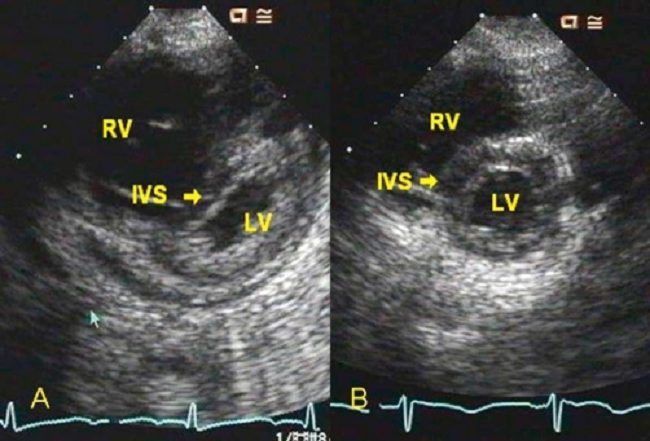

Gambar 1. Ekokardiografi cor pulmonale

Diagnosis cor pulmonale dapat ditegakkan jika terdapat tanda dan gejala gagal jantung kanan, disertai dengan penyakit primer pada sistem pernapasan. Kateterisasi jantung kanan adalah modalitas diagnosis yang paling akurat, tetapi paling invasif. Oleh karena itu, modalitas diagnosis yang lebih sering digunakan adalah echocardiography.[1,5]